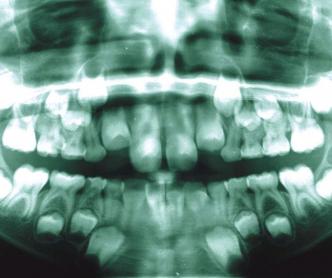

Übersichts-Röntgenaufnahme

Einzelzahn-Aufnahmen

Um den Zustand der Zähne oder Zahnkeime festzustellen, sind Röntgenaufnahmen bei allen kieferorthopädischen Behandlungen zwingend erforderlich.